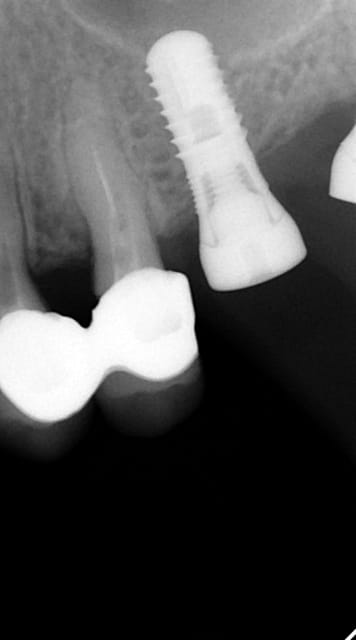

En ce qui concerne la précision, dans ce cas là et pour eviter une augmentation, j ai du placer l implant en mesio palatinal ( voir radio initiale)

En mesurant la hauteur de l os dans le septum ( dans le DVT), celui était seulement de 3 mm. Voilà pourquoi l´implant n est pas dans le septum. L´os a été condensé,la stabilité primaire a donc pu atteindre 50 Ncm.

Pour ceux que ca interessent, et parce qu on a m a demandé des cas supplémentaires dans le sujet 23 implants rehabilitation totale, voici un autre cas d implantation immédiate avec la technique minimalement invasive et condensation grace aux forets.

Le patient a reçu un traitement il y a dix ans dans le maxillaire et dans le 4eme quadrant.Comme on peut le voir j´ai du extraire quelques dents au maxillaire: 35 37 et 45.

Le septum de la 37 a été foré avec un foret conique 3 faces.

J ai planté à 60 Ncm sans fracturer le septum.Juste après l opération , les prep caps en zircon ont été cémenté.La restauration définitive 34 jusqu` à 37 été fixé 2 semaines après l implantation avec implantlink (detax). Après un an, le bridge a été retiré facilement pour voir l´état de la gencive et faire une radio de contrôle.On la re ossifiction est satisfaisante et que la gencive "aime" le zircon.